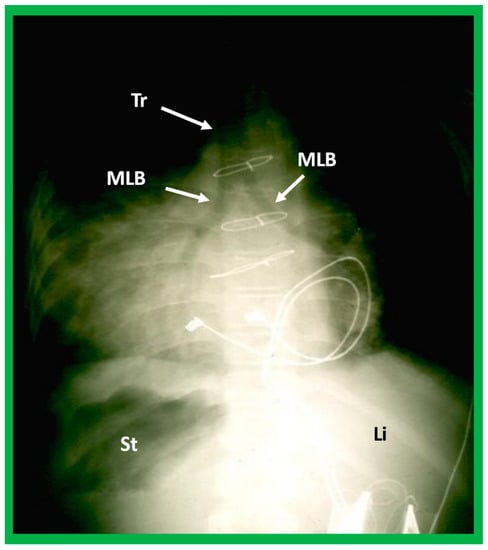

5.2.3. Tracheobronchial Tree Pattern

In typical patients with situs solitus, the bronchus on the right side is short and wide and descends somewhat steeply, whereas the bronchus on the left side is longer and narrower than the right bronchus and descends rather horizontally (Figure 22A and Figure 23). On the contrary, in patients with situs inversus, the tracheobronchial tree configuration is inverted (Figure 22B and Figure 24) [2,3,4,5]. The tracheobronchial tree pattern seems more correct than the above two approaches to identifying the atrial situs [2,26,27]. Tomography has been used in the past [27] to more accurately determine bronchial morphology and measure the bronchial lengths but is not routinely used at the present time because of increased radiation exposure associated with tomography and the availability of other imaging studies.

If both bronchi (right and left) have the appearance of morphologic right bronchi (Figure 21 and Figure 22C), asplenia syndrome is likely to be present, whereas morphologic left bronchi on both sides (Figure 22D and Figure 25) is indicative of polysplenia syndrome [2,3,26,27]. Exceptions to these observations have been seen but are uncommon [3,28,29].

Figure 25. A highly penetrated chest roentgenogram in an anteroposterior view of a child with dextrocardia associated with situs inversus demonstrates bilateral morphologic left bronchi (MLB); the patient was found to have polysplenia syndrome. Sternal wires and pacemaker artifacts (not labeled) from the previous operation are also seen. Li, liver, St, stomach; Tr, trachea.